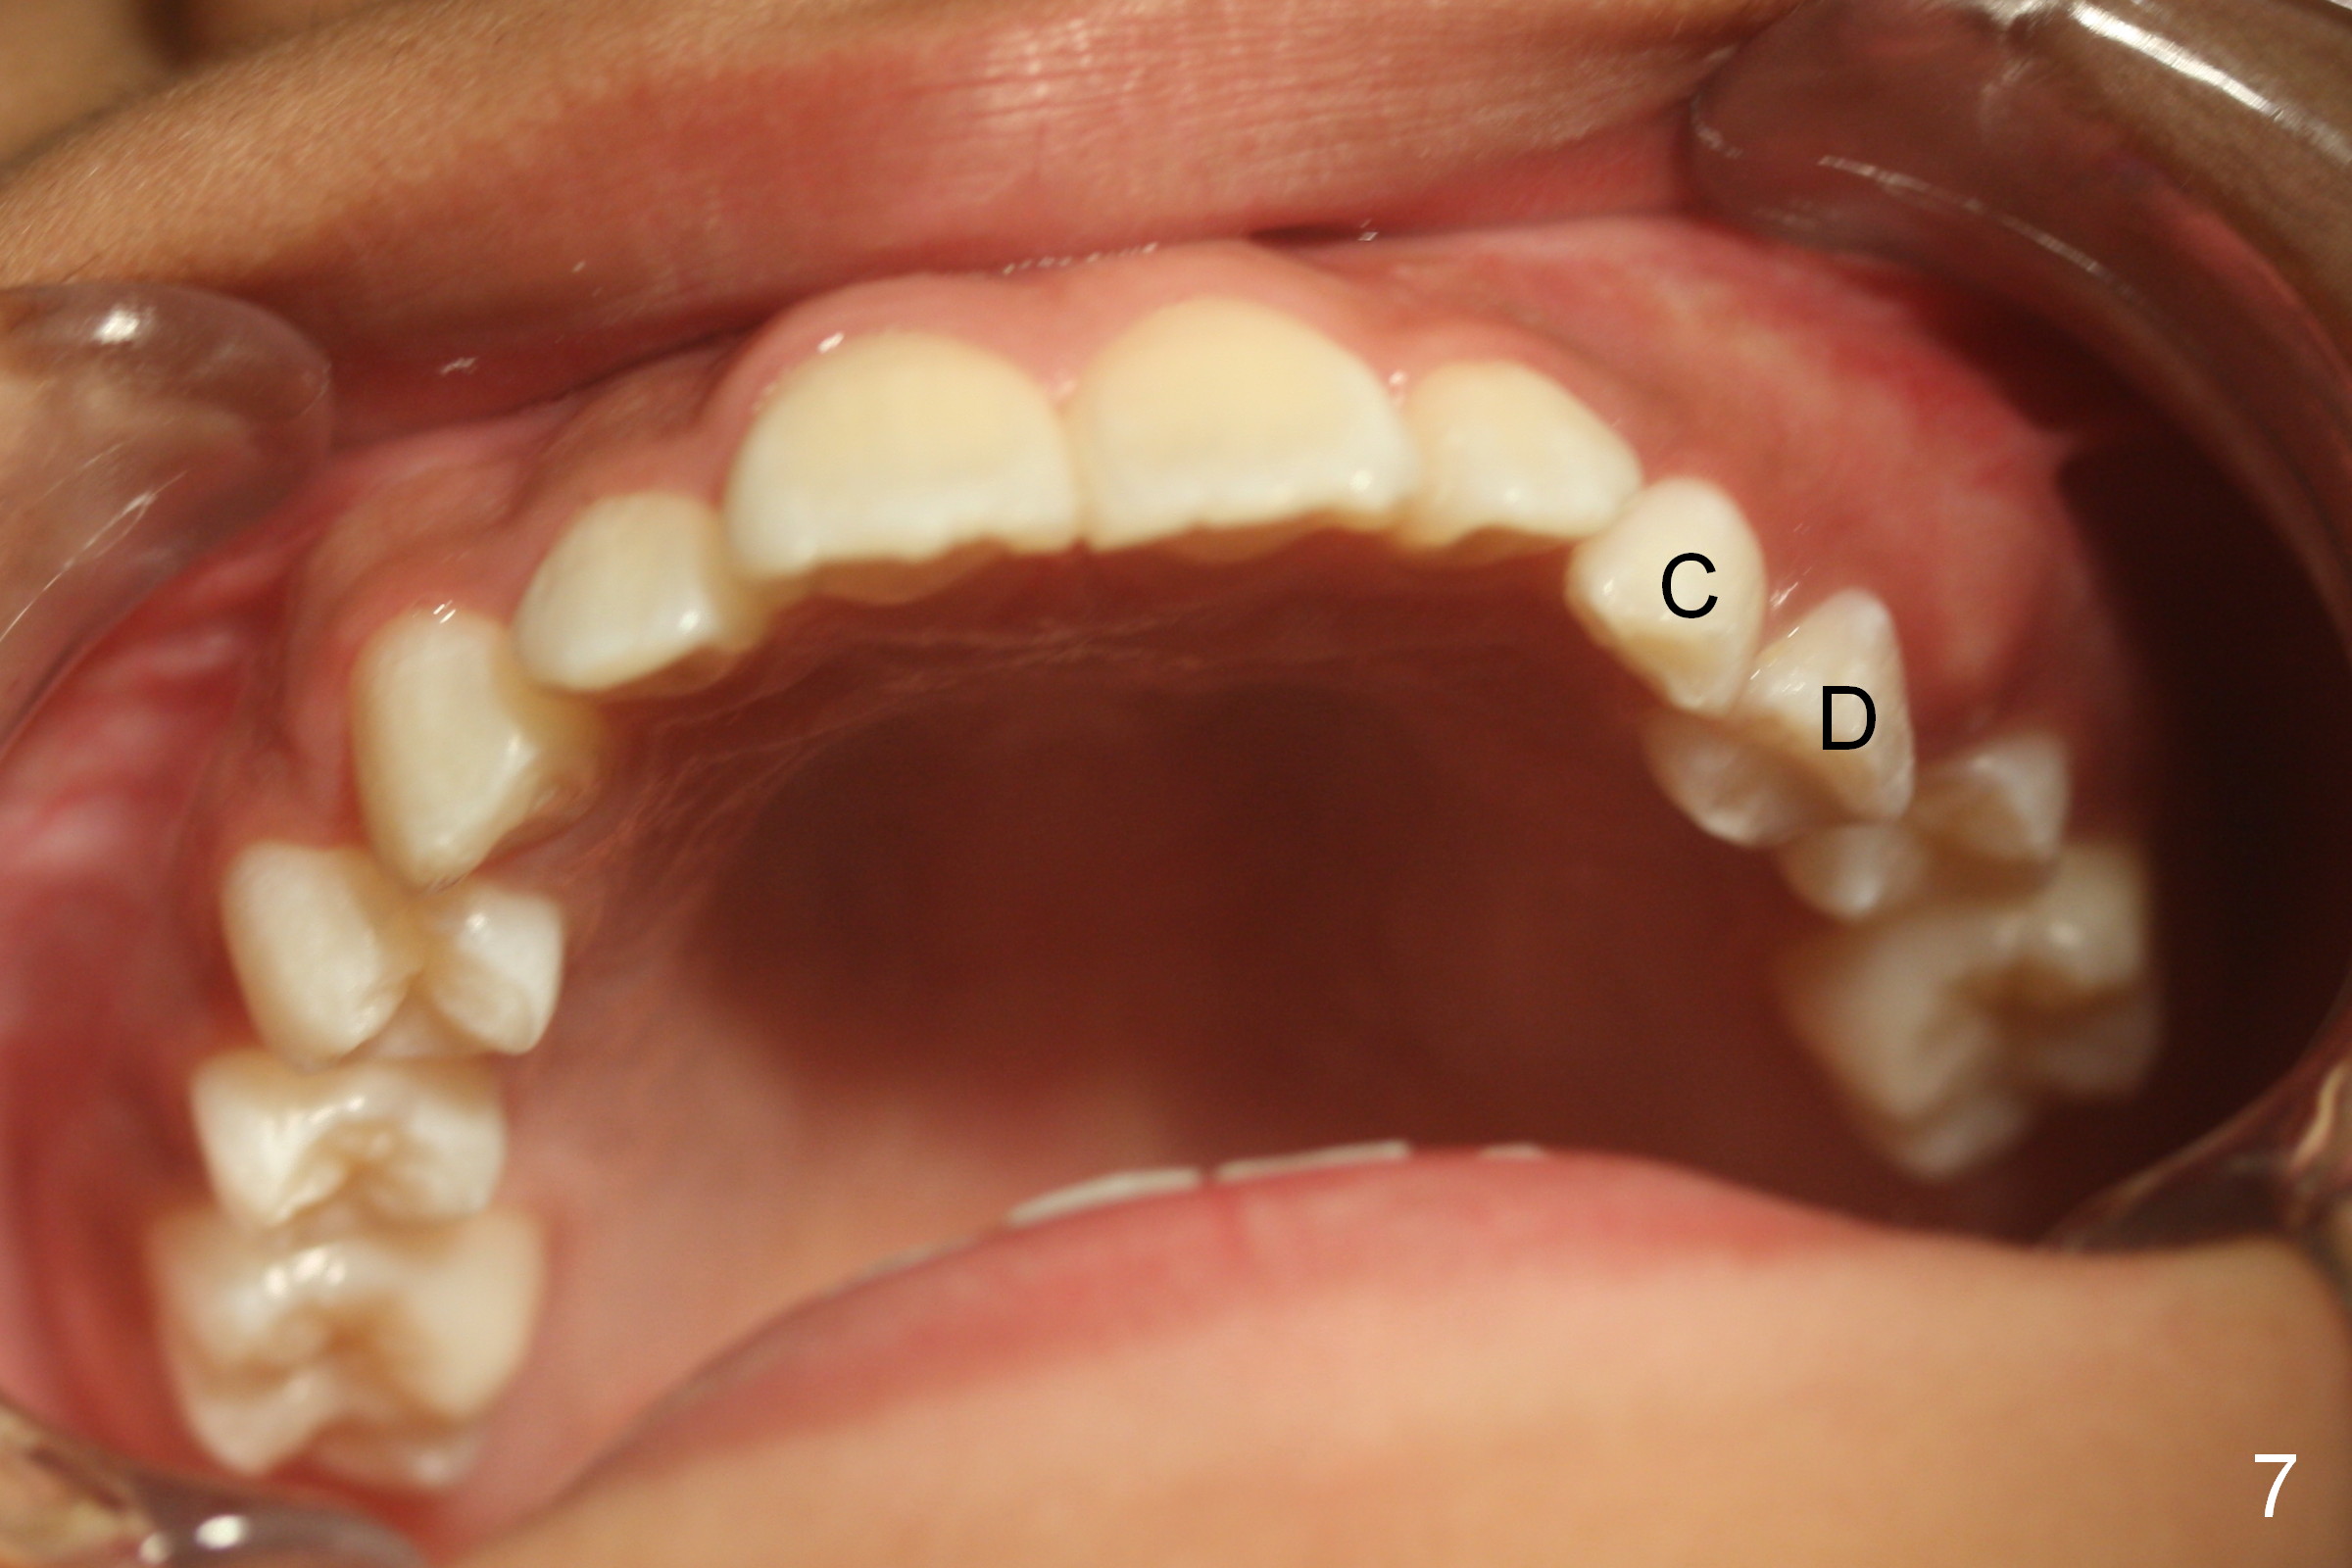

A 11-year-old boy has history of asthma. His father has sleep apnea with similar Class II malocclusion. Pan was taken for the boy 3 years ago (Fig.1). His mother wants to have orthodontic treatment as early as possible, because of protrusive upper anterior teeth. The dentition is permanent except the upper left canine and 1st molar (Fig.7,10,12,13 C, D). It appears that there is bilateral Class II occlusion at canine by half a tooth (Fig.9-12). The malocclusion and facial profile can be easily corrected with extraction of the upper 1st bicuspids.